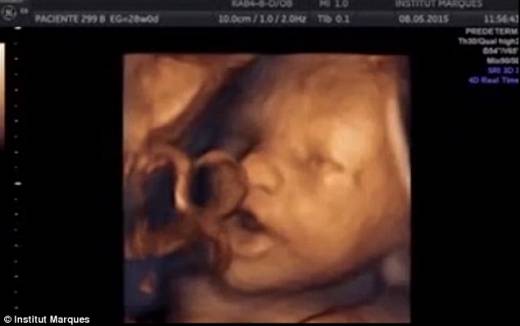

연구진은 임신 14~39주차에 해당하는 임신부의 질을 통해 일종의 ‘스피커’를 삽입한 뒤 음악을 재생했다. 그런 뒤 초음파로 태아의 움직임을 관찰한 결과 음악을 들은 태아가 혀와 입을 크게 움직이며 반응하는 것을 확인했다.

이번 연구에서 가장 눈길을 끈 것은 태아가 고작 임신 16주에도 소리를 들을 수 있다는 사실과, 소리를 듣고 입과 혀를 움직이는 발성 동작을 보일 줄 안다는 사실이다. 이러한 발성동작은 신생아들이 언어를 습득하기 이전에 보이는 것과 같은 동작으로서, 구강구조를 통해 ‘노래’를 하듯 음악에 반응한다는 것을 확인한 것이다.